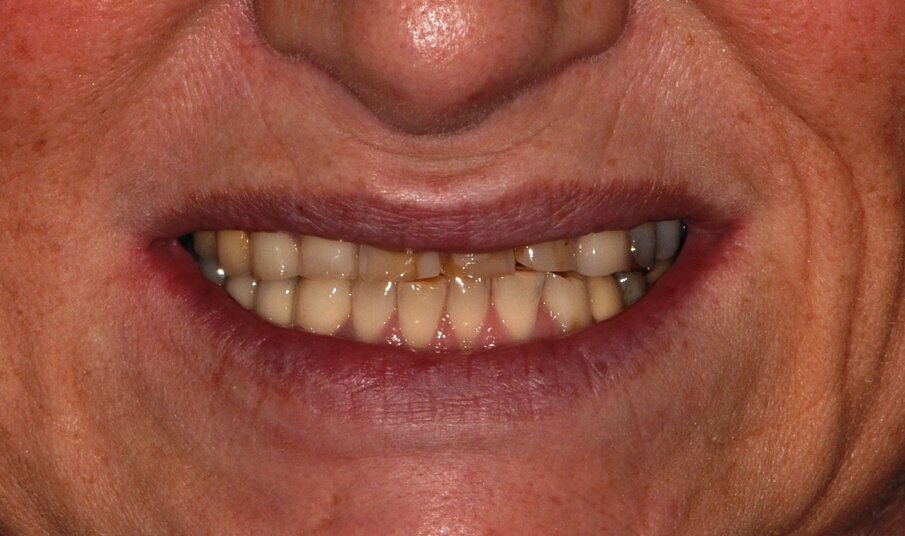

Fig. 1: Clinical baseline situation

Fig. 15: Preoperative smile and lip profile

A 55-year-old woman presented at the Department of Preventive Dentistry, Periodontology and Cariology of the University of Göttingen. The clinical and radiological examination revealed an adult dentition that had been insufficiently treated with fillings and dental restorations and exhibited a loss of vertical dimension of occlusion (Figs. 1 and 2). Insufficient restorations (secondary caries) were found on teeth 24, 25, 26, 27, 37, 38, 35, 47, and 48. The existing bridge (17–15, 14) was insufficient due to extensive ceramic fractures. Part of the hard tissue of the upper maxillary incisors with their — sometimes extensive — composite restorations had been lost to attrition and vestibular erosion. The endodontic treatment of tooth 34 was adequate, while tooth 46 required a primary endodontic treatment due to an irreversible pulpitis. All other teeth were vital and free of symptoms. The periodontal findings showed moderate gingivitis (periodontal screening index < 3 in all sextants). Teeth 13, 23, 24, and 43 additionally exhibited vestibular gingival recessions.